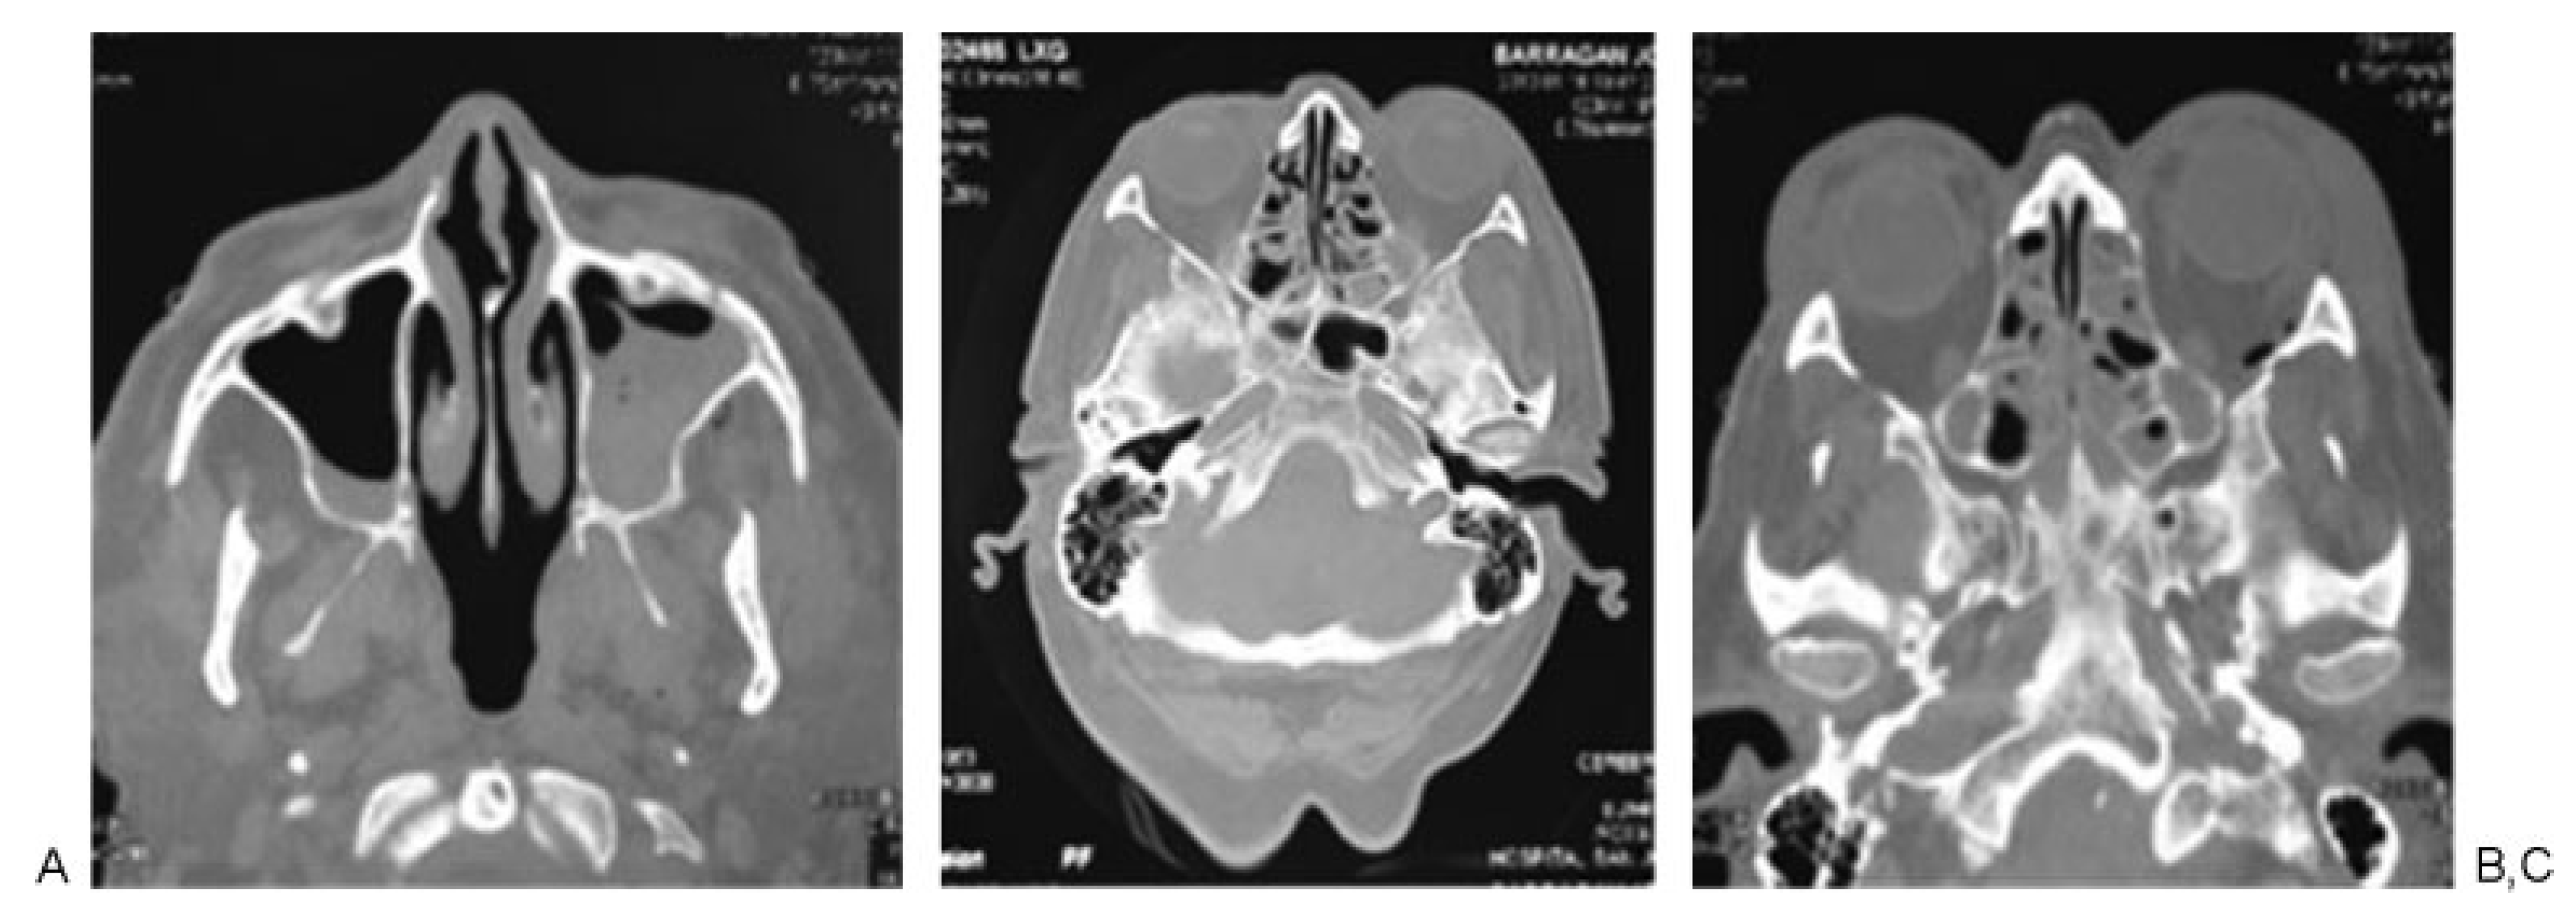

Figure 2. Patient 1: high-energy trauma and panfacial fractures. (A) Zygomatic arch, malar, and upper jaw fractures. (B) Sphenoid sinus fracture. (C) Computed tomography three-dimensional reconstruction showing the fractures at the middle third and jaw.

According to Manson’s classification, 17.9% (n ¼ 38) of the trauma in the group corresponded to high-energy trauma, followed by medium-energy trauma at 33.5% (n ¼ 71) and low-energy trauma at 48.6% (n ¼ 103). Among the patients with high-energy trauma, 31.5% (n ¼ 12) had combined fractures of the sphenoid bone and sphenoid sinus and 31.5% (n ¼ 12) had sphenoid sinus fractures only. In contrast, 1.4% (n ¼ 3) of patients with middle-energy trauma had sphenoid bone fractures, 5.6% (n ¼ 4) of the patients had sphenoid sinus fractures, and 4.2% (n ¼ 3) of the patients had sphenoid bone and sphenoid sinus fractures. In the low-energy trauma group, only 1 patient presented sphenoid sinus fracture (0.97%; Table 3; Figure 2, Figure 3 and Figure 4).